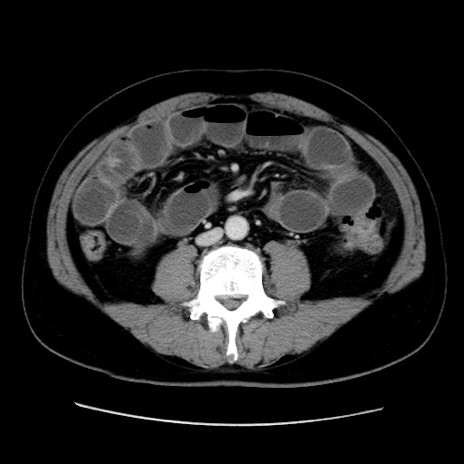

冠状断像